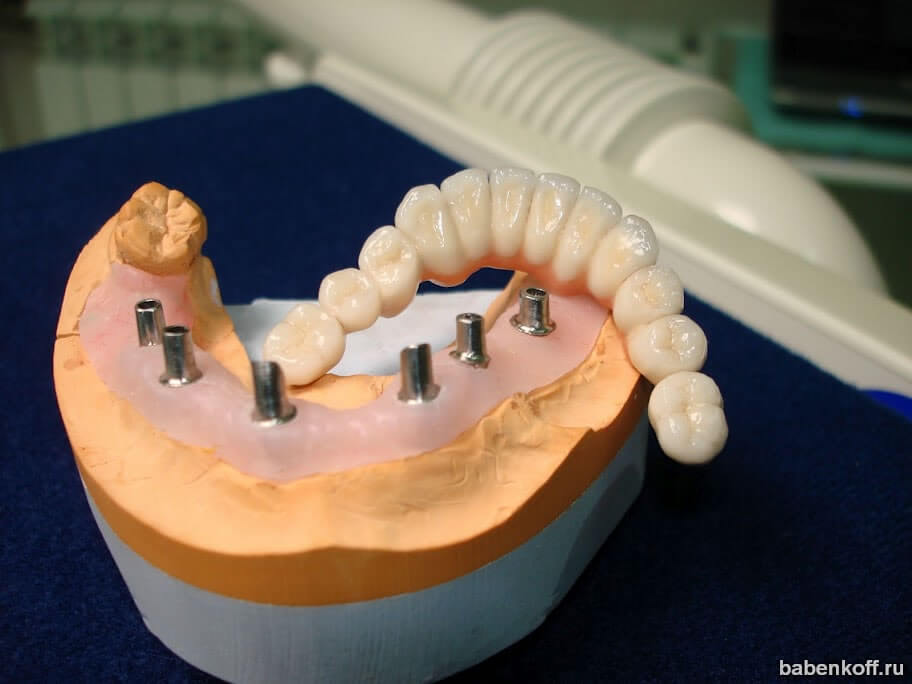

Современные коронки на зубные импланты: виды и фото-примеры

Раздел: Необычные решения